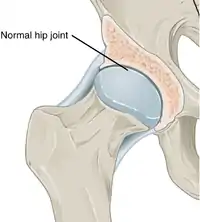

Histopathology of osteoarthrosis of a knee joint in an elderly female In a healthy joint, the ends of bones are encased in smooth cartilage. Together, they are protected by a joint capsule lined with a synovial membrane that produces synovial fluid. The capsule and fluid protect the cartilage, muscles, and connective tissues.

In a healthy joint, the ends of bones are encased in smooth cartilage. Together, they are protected by a joint capsule lined with a synovial membrane that produces synovial fluid. The capsule and fluid protect the cartilage, muscles, and connective tissues. With osteoarthritis, the cartilage becomes worn away. Spurs grow out from the edge of the bone, and synovial fluid increases. Altogether, the joint feels stiff and sore.